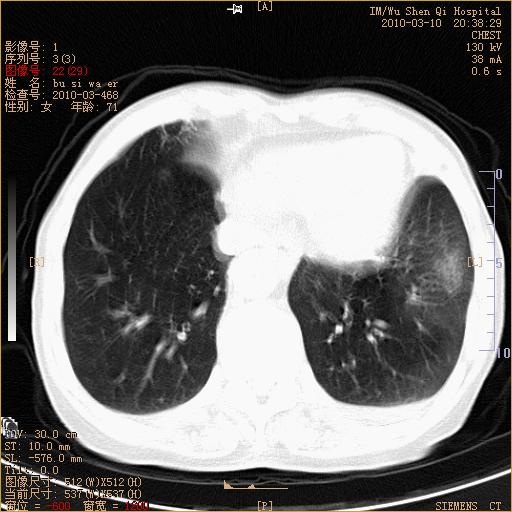

以下是引用随光逐影在2010-3-11 0:41:00的发言:[br]1)考虑左肺及右肺上叶继发性肺结核并左肺炎症感染。2)左侧支气管内膜结核可能;建议必要时行纤支镜检查。3)肺气肿。4)心包膜增厚(或少量心包积液)。5)左侧胸腔积液。